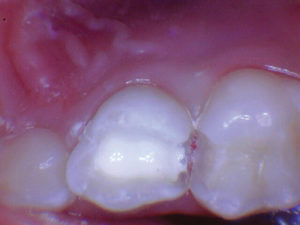

Figura 1. Después del ataque ácido y el uso del agente de unión Scotchbond Universal (3M), los dos molares primarios superiores se restauraron con Activa Bioactive Restorative A2. |

Figura 2. Una vez que se excavó la descomposición y se colocaron los márgenes en superficies sólidas, se colocó un bisel pesado en el esmalte para aumentar la resistencia de la unión y la integridad marginal. El área oscura central era sólida. El diente estaba revestido con una base / revestimiento Activa. |